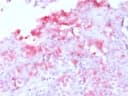

MART-1 / Melan-A Recombinant Antibody

MART-1/Melan-A is a protein antigen that is found on the surface of melanocytes. Antibodies against the antigen are used in the medical specialty of anatomic pathology in order to recognize cells of melanocytic differentiation, useful for the diagnosis of a melanoma. The MART-1/Melan-A antigen is specific for the melanocyte lineage, found in normal skin, the retina, and melanocytes, but not in other normal tissues. It is thus useful as a marker for melanocytic tumors (melanomas) with the caveat that it is normally found in benign nevi as well. [Wiki]UniProt:

RecombinantApplications:

IHC-P, WBFormat: